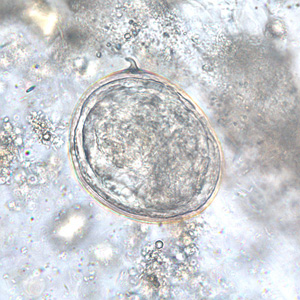

Шистосома Яйца Фото

Шистосома Яйца Фото 111 фотографий